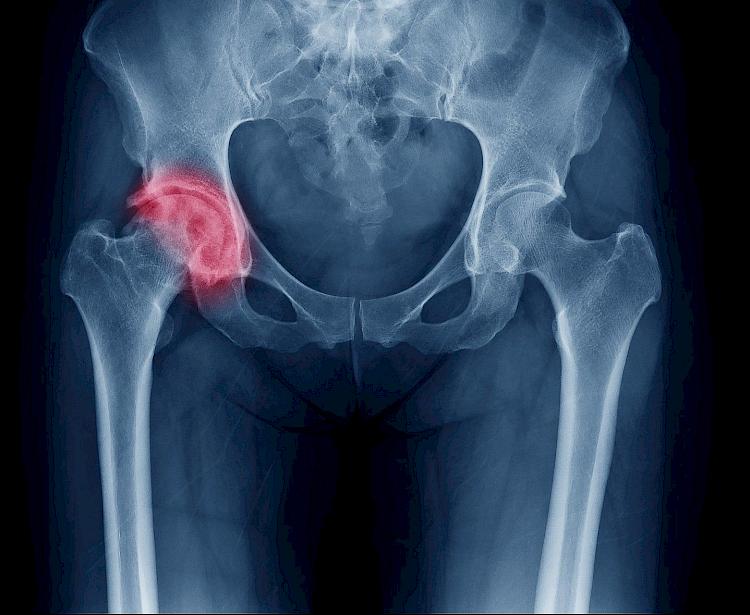

The concern about some metal-on-metal hip replacements, specifically one implant made by a Johnson & Johnson company, called DePuy Orthopaedics, is that implants caused significant problems within the first few years after replacement. In some patients, this issue has been severe, causing permanent injury.

Patients with these metal-on-metal implants have also been found to have high levels of metal ions in their bloodstream.